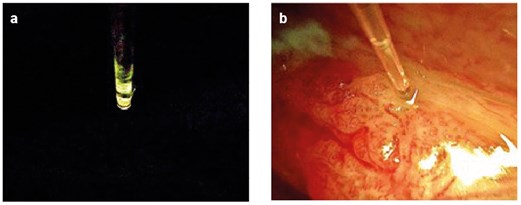

Figure 2: a) Once the tip of the fibre is exactly in the middle of the video screen, it can be fixed. b) The fibre is stable and it is guided by the endoscope to accurately reach the area to be treated.

- The fibre is placed on top of the 30º, 5-mm-diameter endoscope (the field of view with an endoscope of lesser diameter is unsatisfactory).

- The best position of the fibre is achieved by looking at the video monitor. Once the tip of the fibre is exactly in the centre of the screen (Figure 2), it is fixed with Steri-StripTM. The first band of Steri-Strip™ is placed a couple of millimetres away from the superior edge of the endoscope, firmly holding the fibre and surrounding the entire circumference of it, and reinforcing with a second band over the first one. Then two more bands are used to hold the fibre in the same manner in the middle and posterior ends of the endoscope (Figure 3). Recently, a disposable custom-made steel tube to pass the fibre through has been tried, fixed just the same way on top of the endoscope. The advantage of the latter is that it is easy to interchange 300 µm and 400 µm fibres as needed (Figure 4).